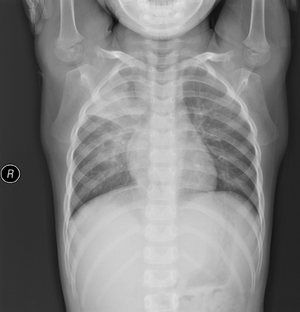

Right upper and middle lobe infiltration in a individual with mycoplasma pneumonia.

M. pneumoniae infections can be differentiated from other types of pneumonia by the relatively slow progression of symptoms. A positive blood test for cold-hemagglutinins in 50–70% of patients after 10 days of infection (cold-hemagglutinin-test should be used with caution or not at all, since 50% of the tests are false-positive), lack of bacteria in a Gram-stained sputum sample, and a lack of growth on blood agar.